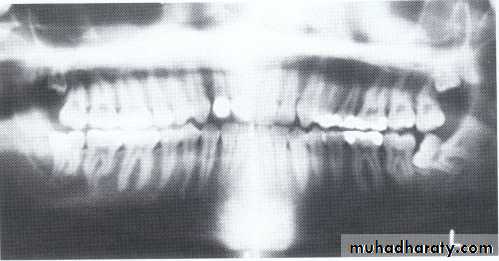

Dentin dysplasia, type I. panoramic & periapical films of the same case show the short and poorly developed roots, obliterated pulp chambers and root canals, and periapical inflammatory lesions.

Dentin dysplasia, type II. panoramic &periapical films of the same case show obliteration of the pulp chamber, reduction in the caliber of root canals, and pulp stones obscuring the flame-shaped pulp chambers.

Periapical inflammatory lesions are associated with some of the mandibular anterior teeth.